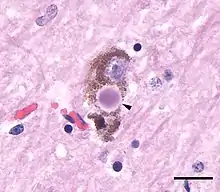

Another hallmark of PD pathology is the development of Lewy bodies (LBs) in dopaminergic neurons which are protein aggregates that impair neuronal function. A major component of the structure of these LBs is α-synuclein which becomes phosphorylated followed by aggregation in pathological conditions. Under normal conditions, α-synuclein remains mostly unfolded with some parts of the protein folded into α-helical structures, however, in PD, it assumes a β-sheet amyloid structure which is highly susceptible to aggregation.[6] Due to dietary differences, South Asians tend to consume higher levels of curcumin, a strong anti-oxidant and anti-inflammatory agent, which has been observed to attentuate α-synuclein aggregation.[7] However, variation in LB and α-synuclein pathologies in the South Asian population is heavily under studied and needs to be further elucidated.